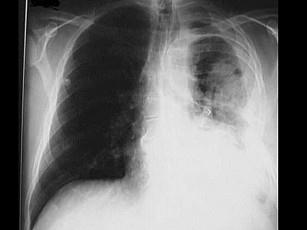

问题 男,28岁,因咳嗽、胸痛、高热入院,左胸穿刺抽出黄色脓液,稠厚,不臭,摄胸片如图所示,为指导治疗,下述病史中哪项最有意义 ( )

选项 A、2周前有“上感”史 B、1周前有左侧肺炎史 C、1个月前有左前臂伤口感染史 D、2周前有左侧胸外伤史 E、半年前有左侧肺结核史

答案 B